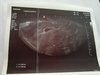

Czasami mamy przeczucie, ze jednak cos jest nie tak. Wczoraj bylam na wizycie, plamienia rozowe. W badaniu usg gs bez cech odklejania z widocznymi wewnatrz dwoma roznej wielkosci ys. W rzutach przydatkow bez ech patologicznych. Plamienia mialy byc niby gdzies z obok. Jest tylkotjeden pecherzyk z dwoma cialkami. Dzis rano bol brzucha, plamienie przeszlo w krwawienie. O 15 wylecial mi pierwszy skrzep. Pojechalismy na kopernika, tam bezradna pani doktor, nie mamy jak pomoc, ani nie zatrzymali mnie, nic. Lekow dodatkowych tez nie dali. Zrobila usg, pecherzyk jakby sie osunal i zmienil ksztalt. Zanim weszlam do gabinetu myslalam ze juz i tak koniec, bo bylam na toalecie a tam galareta ze mnie leciala na kilka cm. Diagnoza po usg, poczatkujace poronienie i skwitowanje, ze raczej nic z tego nie bedzie. Porownalam oba usg po wyjsciu, faktycznie na tym nowym pecherzyk nie jest juz tak okraglx a raczej owalny podluzny. Nie widze tez drugiego cialka zoltego, tylko jedno. Endometrium wczoraj ok 12-13 mm, dzis wedlug jej urzadzenia 12 mm.

Co teraz robic? Bezczynie lezec i czekac az wszystko wyleci lacznie z pecherzykiem? Dodac progesteronu w formie duphastonu? Dodac estrofemu aby utrzymac endometrium? Ona nie wie nic, a w klinice juz nikogo nie ma. Jutro zrobie bete i prog, jak poleciala to wiadomo bedzie ze to koniec, z drugiej strony, czy mozliwa jest galareta i krwawienie jezeli jedno z cialek zoltych obumiera? Tu tez nie wiedziala, wogole dziwne to IP na Kopernika.